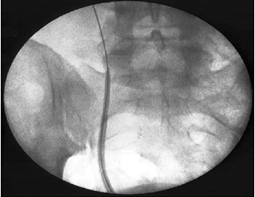

This is a retrospective study analyzing 81 patients who benefited from PCNL (n=45) and URS (n=36) for lower calico stones between July 2012 and June 2015 in the urology department of the Mohamed V military hospital in rabat. The general characteristics of the patients were comparable in the two groups (Age, Gender, BMI). The mode of revelation was often nephretic colic in the PCNL group than in the URS group, in a small number the stone was discovered incidentally. Clinical success was defined by stone-free status or the presence of an asymptomatic residual fragment less than 3 mm. The chi2 test is used to compare the success rate, postoperative complications and transfusion rate, the t test and the witney test were used to compare the quantitative variables. The results are defined as significant for a p<0.05, the statistical analysis is performed using the SPSS software. The majority of patients had a double J catheter 3 to 4 weeks before the URS for passive dilation of the ureter. In the lithotomy position, cetherization of the ureter by a ureteral probe, a safety guide is left in place, an access sheath (45cm for women and 55cm for men) is slipped over the guide under fluoroscopic control (Figure 1).

Figure 1 Access sheath Fluoroscopic image.